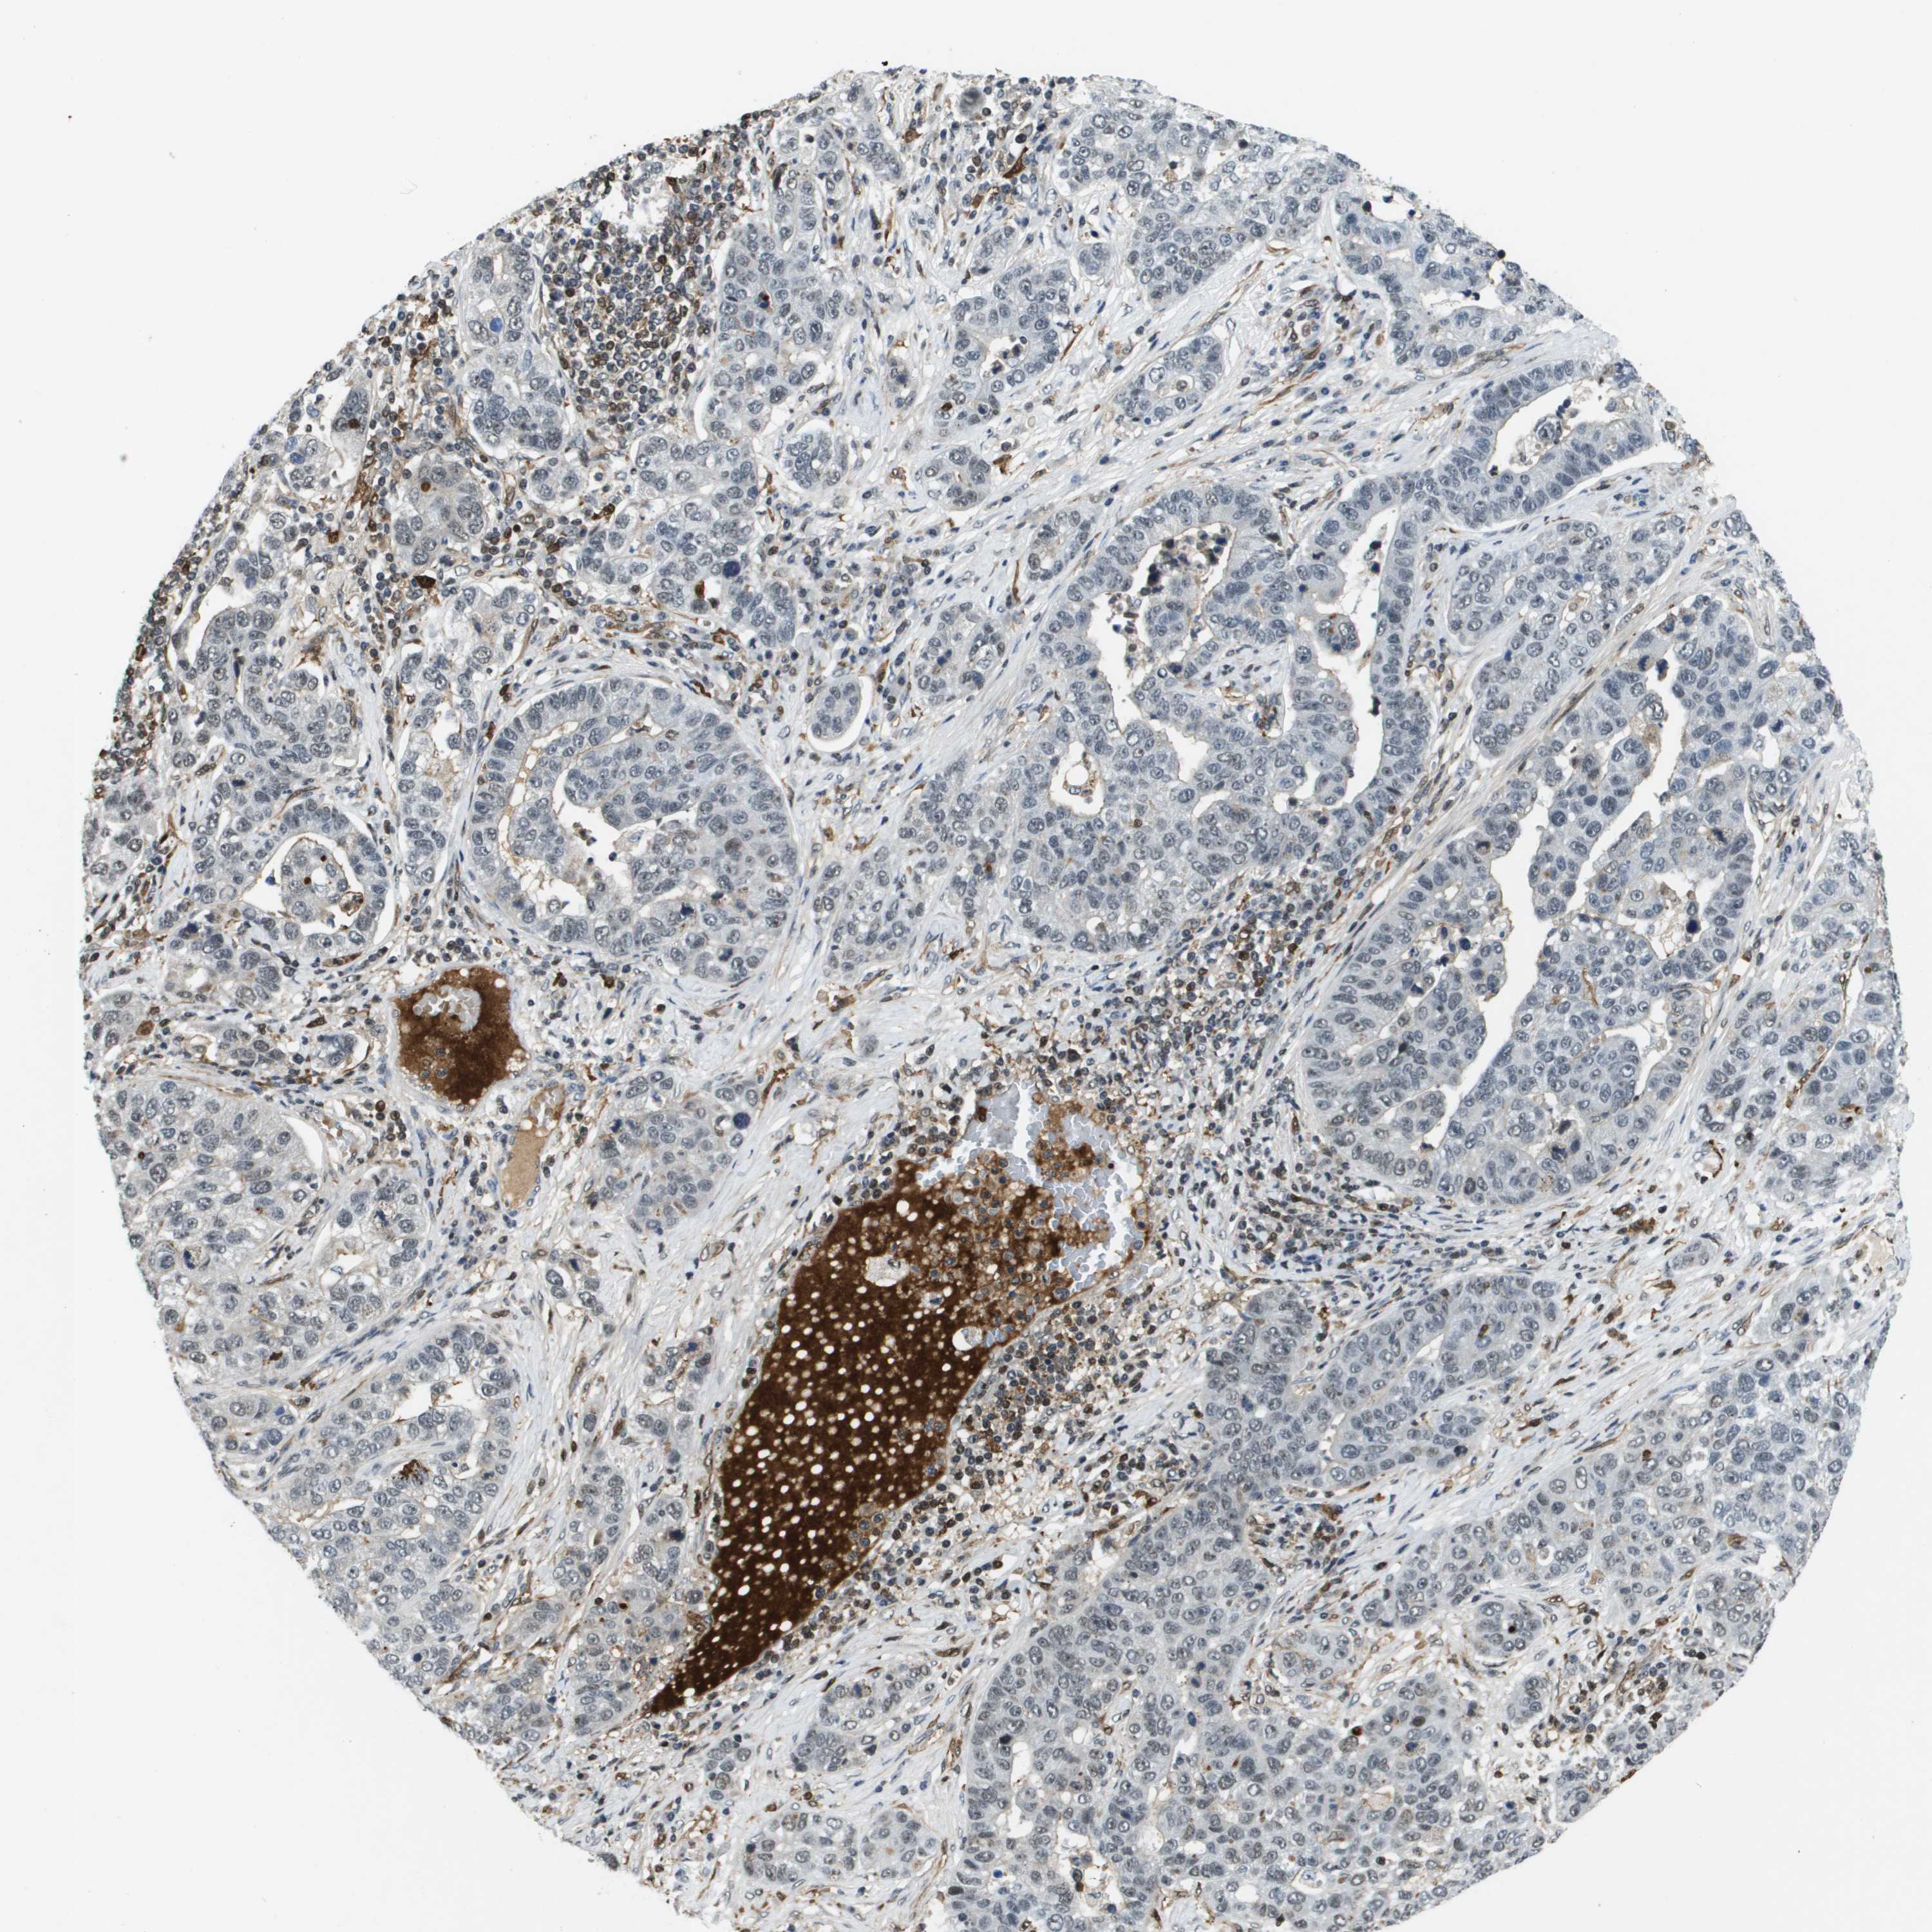

PANCREATIC CANCER - Protein expressioni

A mouse-over function shows sample information and annotation data. Click on an image to view it in a full screen mode. Samples can be filtered based on level of antibody staining by selecting one or several of the following categories: high, medium, low and not detected. The assay and annotation is described here.

Note that samples used for immunohistochemistry by the Human Protein Atlas do not correspond to samples in the TCGA dataset.

Antibody stainingi

Antibody staining in the annotated cell types in the current human tissue is reported as not detected, low, medium, or high, based on conventional immunohistochemistry profiling in selected tissues. This score is based on the combination of the staining intensity and fraction of stained cells.

Each image is clickable and will lead to virtual microscopy that enables deeper exploration of all samples and also displays staining intensity scores, fraction scores and subcellular localization as well as patient and tissue information for each sample.

Antibody HPA016704

Staining

High

Medium

Low

Not detected

Intensity

Strong

Moderate

Weak

Negative

Quantity

>75%

75%-25%

<25%

None

Location

Nuclear

Cytoplasmic/membranous

Cytoplasmic/membranous,nuclear

Adenocarcinoma, NOS